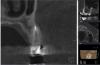

annda Опубликовано 25 марта, 2010 Поделиться Опубликовано 25 марта, 2010 (изменено) так вроде там клыка вообще на снимке нет. это пятерка и семерка. 4 и 6 - отсутствуют. ничего не понимаю, много разных врачей крутили прицельные-панараму и КТ, ничего не увидели ((( скажите куда попросить врача посмотреть внимательно в этом случае. кстати на первом снимке это срез с КТ, поэтому всей 7ки там не видно, конечно. если это имеет значение, то никакой реакции у зуба нет, ни на холодное.горячее, ни при надавливании и постукивании консультировался в уважаемых клиниках - МАПО, 1 МЕд, Artes и Аркадия ( все в Питере)Да,не сориентировалась,прошу прощения.Меня бы заинтересовал срез слева внизу на последнем снимке,рядом с запломбированным каналом(белая точка) похоже есть незапломбированный канал(чёрная точка),пишу с макинтоша,потому тут в Пойнтах не рулю(пока),стрелки рисовать не умею,может,кто из докторов поможет.Пы.сы.не утверждаю,а только предполагаю. Изменено 25 марта, 2010 пользователем annda Ссылка на комментарий

tim91 Опубликовано 25 марта, 2010 Автор Поделиться Опубликовано 25 марта, 2010 Да,не сориентировалась,прошу прощения.Меня бы заинтересовал срез слева внизу на последнем снимке,рядом с запломбированным каналом(белая точка) похоже есть незапломбированный канал(чёрная точка),пишу с макинтоша,потому тут в Пойнтах не рулю(пока),стрелки рисовать не умею,может,кто из докторов поможет.Пы.сы.не утверждаю,а только предполагаю. Спасибо, по поводу каналов на 5ке сам спрашивал, но говорят что их там было два, причем их сдвоили( не знаю термина) когда делали каналы, и получился один канал. Завтра иду на очередную консультацию, попробую обратить внимание врача. А может у меня это нытье идти от гайморовой? Я так понял зуб прямо в ней расположен (((. Хотя ЛОР, который КТ изучал, сказал что часто так бывает. Еще вопрос. Есть возможность сделать любую физиотерапию , только непонятно что именно, врачи предлагают спросить физиотерапевта, а где его взять (( Там где могу сделать есть только сестра, которая сама ничего не знает, боится навредить. Ссылка на комментарий

Fred Опубликовано 26 марта, 2010 Поделиться Опубликовано 26 марта, 2010 Спасибо большое, был бы признателен. Сделаю сейчас. Был сегодня опять на консультации у очень хорошего эндодонта, так терять зуб не хочу совсем, предлагает два варианта - заново перепломбировать 5ку, хотя гарантии никакой, конечно нет, он на ней очагов не видит ((. Второй вариант сделать разрез сбоку отрезать сверху 1-2 мм и запломбировать с той стороны, но этот вариант страшный, так как близко пазуха ((. Еще вопрос, могут ли такие явные боли сверху отдавать снизу? Там есть не очень симпатичный зуб тоже (( Но вроде каналы тоже в норме со слов врачей КТ выложил тут http://ifolder.ru/16989198 Посмотрел Вашу КТ. Канал в пятерке один, второго ни канала, ни корня нет, пломбирование достаточно качественное, но что меня настораживает, так это утолщение слизистой оболочки верхнечелюстной пазухи как раз у того зуба. Может быть, что на КТ выглядит качественная пломбировка, но реально, все-таки, происходит хроническое инфицирование. Хотя пригледевшись, все-таки на КТ небольшое "поражение" у верхушки этого зуба увидеть можно.Если в зубе нет вкладки, я бы советовал перепломбировать его через мостовидный протез. Если там есть штифт или вкладка, наверняка, разумнее было бы срезать верхушку корня. При такой КТ 5ки не может быть чисто на прицельном снимке.Клык вроде нормальный,а вот 5ка -никакая.Перелечивать обязательно.Ань, научись томограммы читать, семерка, которую ты приняла на КТ за 5-ку, имеет качественно пломбированные все 4 канала! Я понимаю, что можно зуб перепутать, но понимать, что по МПР на КТ судить о пломбировании каналов нельзя, если всей КТ нет, просто обязательно. А ты перелечивать ... Ссылка на комментарий